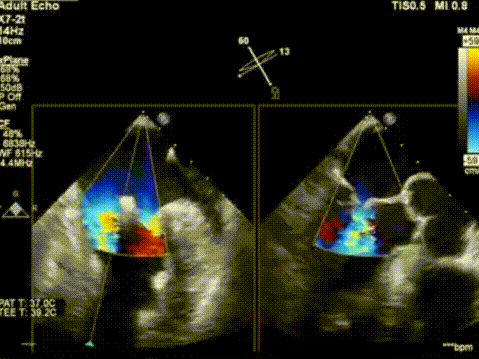

术后TEE显示,二尖瓣夹植入后反流减少